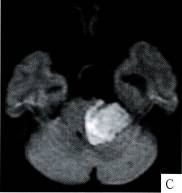

3.定性诊断:①囊性均质占位;②边界清楚,脑实质及颅骨无侵犯,考虑为良性占位;③DWI呈高信号;④增强后病灶及囊壁均无明显强化,说明病变无血供。本例经病理(图G)证实为:表皮样囊肿。

4. 鉴别诊断:本例需要鉴别的占位:①蛛网膜囊肿:发生在桥小脑角区较少见,单凭信号难以区别二者,FLAIR、DWI对鉴别有较大帮助,表皮样囊肿由于病灶 内角化物和蛋白质不能完全被抑制,水分子的运动受限制,则FLAIR表现为稍高于脑脊液信号,DWI表现为高信号;②听神经瘤囊变:多伴有听神经增粗,增 强后囊壁可见强化,常有内听道扩大;③脑膜瘤完全囊变:较少见,“脑膜尾”征较具有特征性。